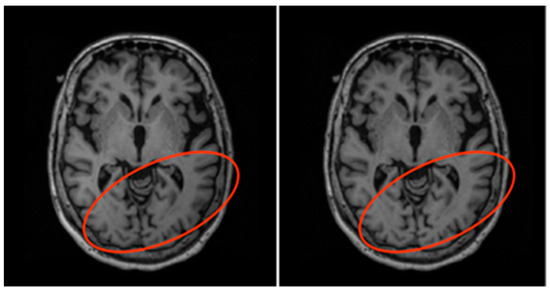

Figure 6.

Before (left) and after (right) N4ITK bias field correction. Notice the slight change in shade of the circled region.